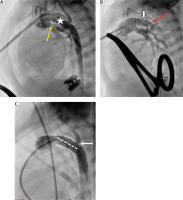

Preceding a stent implantation, a 7F sheath was inserted into the pulmonary artery and subsequent angiography showed the size and length of the DA and made it possible to establish a landing zone which started at the origin of the left pulmonary artery (LPA). Balloon expandable stents (Palmaz Genesis) ranging in size from 7 mm/12 mm to 10 mm/19 mm were deployed into the arterial duct. Unfortunately, if the stent was too short (less than 15 mm) or too narrow (less than 8 mm), the procedure was complicated with stent dislodgment or DA proximal or distal stenosis with the need for additional interventions. Another crucial problem was obturated retrograde flow into the aortic arch due to the stent or isthmus stenosis limiting the coronary and cerebral flows (Figures 3–5).

Figure 5

Arterial duct stent dislodgment into the descending aorta. A, B – Pulmonary artery angiography in lateral view showing proximal arterial duct stenosis (white arrows). A stent Palmaz Genesis 8 mm/15 mm deployed in the distal arterial duct. White circle indicates a dislodged stent Palmaz Genesis 7 mm/12 mm following re-dilation. B – Tight pulmonary arteries band (yellow arrow). C – Aortic arch angiography showing extremely hypoplastic ascending aorta (white arrow)